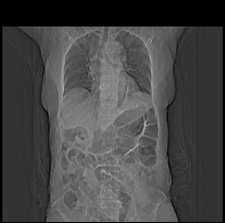

患者,女,75岁。腹痛,体黄5日,膝胸位时腹痛缓解。肝功能明日出来。彩超提示胆总管占位,未见血流信号。心电图提示s-t段改变。患者体质较弱,未能增强。

胆总管多发结石伴肝内外胆管轻度扩张。

胆总管上段,腔内有软组织密度影 ,ct值36-44hu。大家看有没有胆管癌的可能。

典型胆总管多发结石;增强扫描前后ct值是否发生改变是鉴别结石与占位的依据。

典型的胆总管多发结石。在没有增强的情况下,暂不考虑其他。

胆总管多发结石伴肝内外胆管扩张。